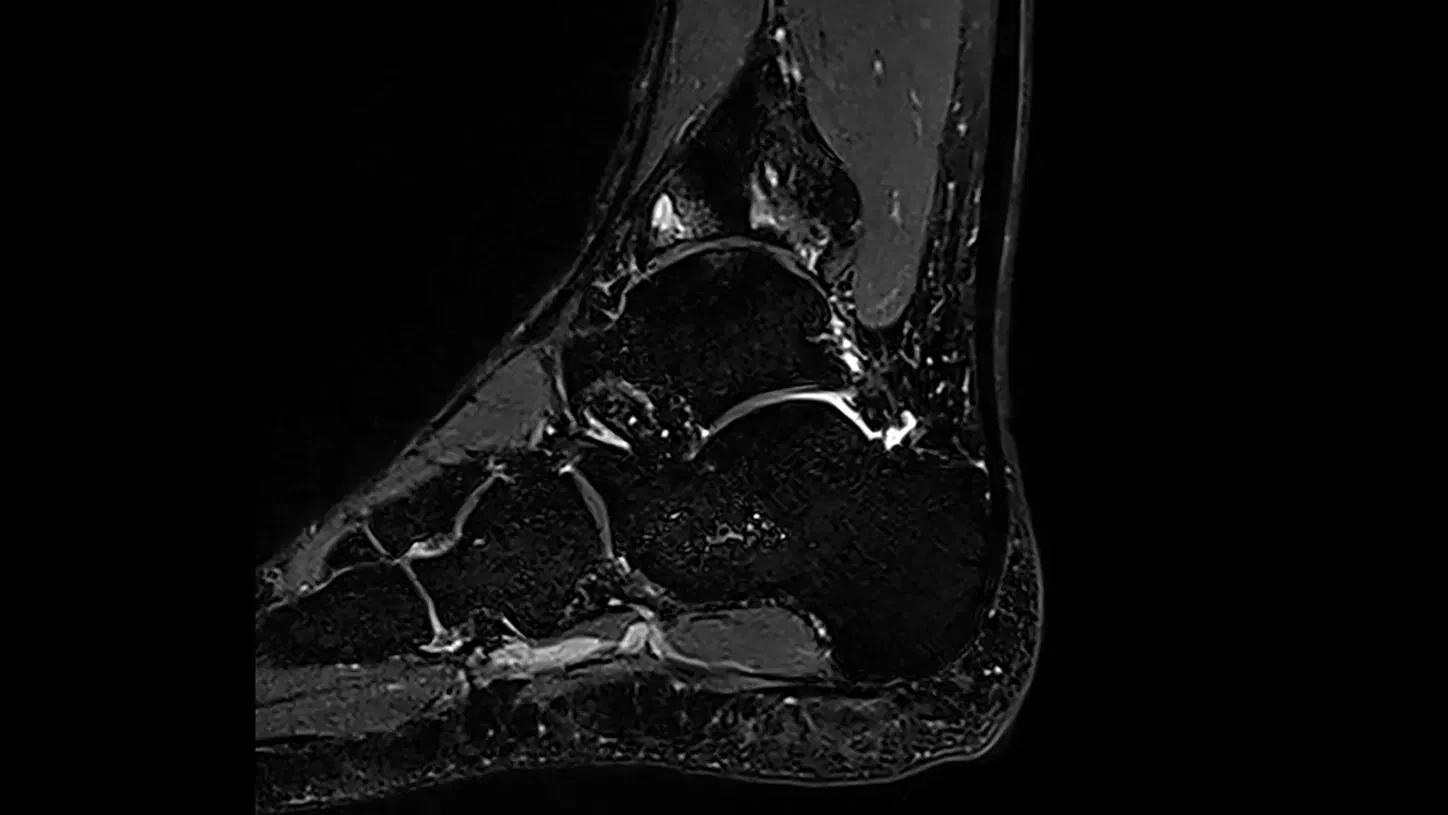

Clinical use

Users can expand precision medicine using high-resolution MR images and accomplish many things clinically.

Image Credit: Siemens Healthineers